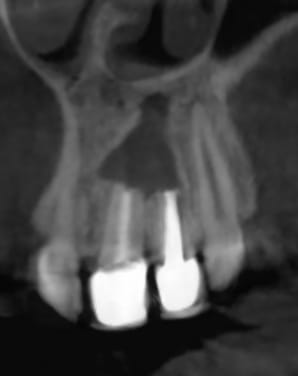

Panostandard 20190423 l9b35r - Eugenol

Elle consulte pour remplacer toutes les dents manquantes, réparer toutes celles qui faut réparer, mais surtout pour son sourire qui la complexe à cause de la 21 et 22 (couronne céramo-métallique moche, couleur plus saturée que la 11 et 12, métal visible, coloration violette de la gencive...), grande cicatrice au niveau péri apicale avec fistule et un peu de pus à la pression, absence d'os à laquelle il faudrait remédier...

Elle revient demain, je ferais une rétro et un cone beam.